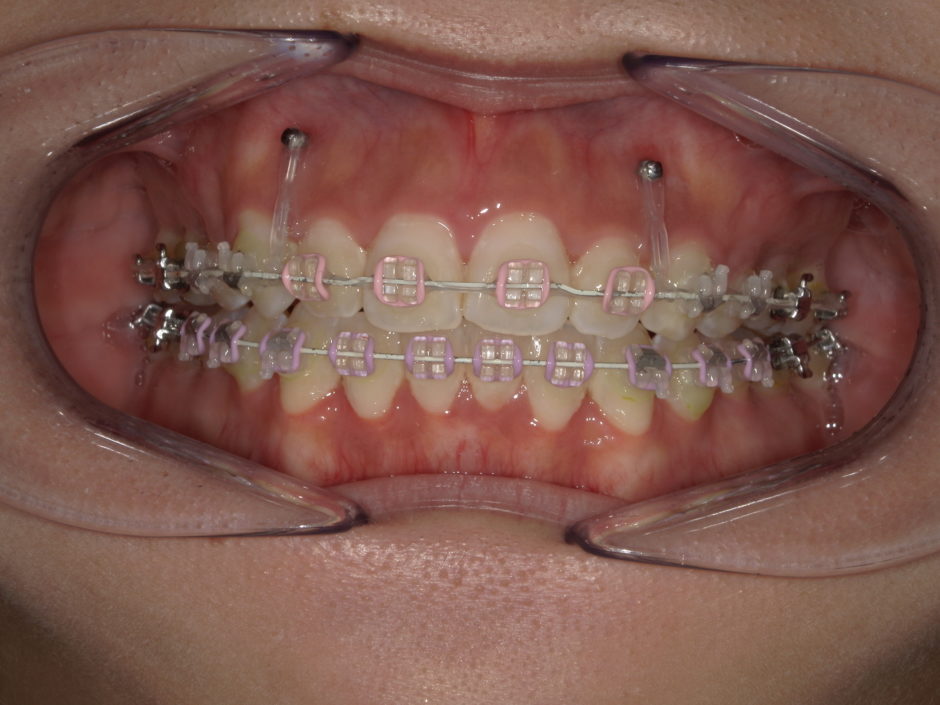

矯正中でのガミースマイル処置は前歯あたりの歯茎にアンカースクリューを打ち上に持ち上げる方法です。

矯正期間が半年程延びる可能性がございますが、外科処置が不要になるケースもございますので